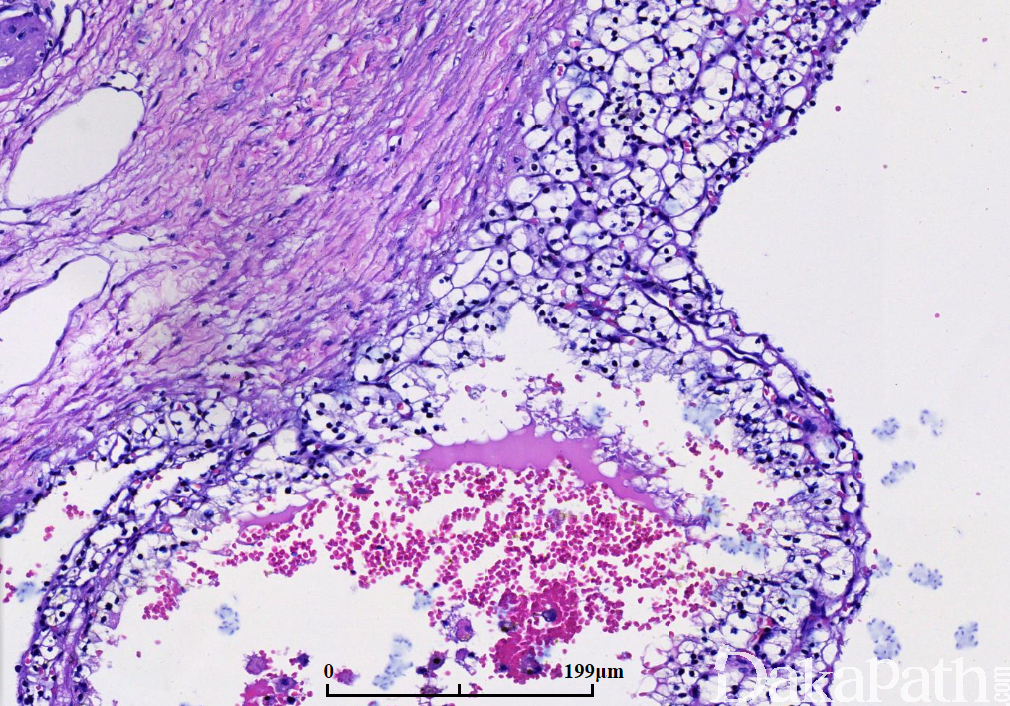

多数囊腔内衬覆单层上皮,细胞胞质透明或淡染,细胞核小而圆,染色质深染而致密,无核仁或小核仁(1-2 级);

有时内衬上皮脱落、消失,偶见内衬复层上皮,或有小乳头;

囊腔间隔由纤维组织构成,常有致密的胶原,部分间隔内可见灶状透明细胞,这些细胞与囊腔的内衬上皮相似,呈小灶状或簇状聚集,不形成大的结节,似组织细胞或淋巴细胞,周围有收缩的人工假象; 6.20%以上病例间隔内有钙化,偶见骨化生;